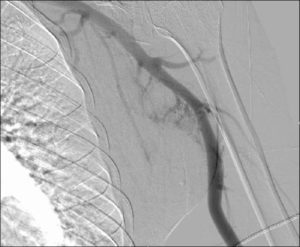

Interventional Radiology (IR) also known as Angiography.

Interventional radiology (IR) is a medical specialty that performs minimally invasive treatments using x ray imaging for procedure guidance. Interventional radiologists use x-ray imaging to guide small instruments, like catheters, through blood vessels and organs to treat a variety of diseases.

An X-ray exam of the arteries and veins to diagnose blockages and other blood vessel problems; uses a catheter to enter the blood vessel and a contrast agent (X-ray dye) to make the artery or vein visible on the X-ray.

Some examples of angiography procedures include angioplasty, stenting, thrombolysis, embolization, radiofrequency ablation, and biopsies. These procedures can treat or help symptoms of vascular disease, stroke, uterine fibroids, or cancer.